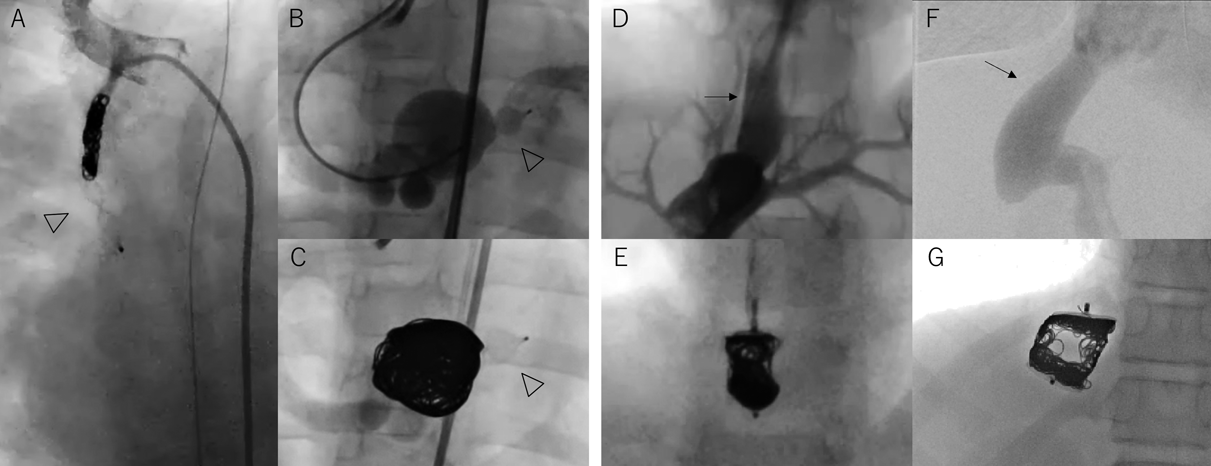

Fig. 7 AVP併用例

A)3.5 mmBTシャントをAVP4 5 mm(矢頭)をAnchoringとして留置し上流にコイルを追加して完全塞栓した.B, C)右冠動脈左室瘻で非常に血流が速く左室への脱落リスクがあったが,左室開口部にAVP4 8 mm(矢頭)を留置し手前の瘤をコイルで充填して完全塞栓した.D, E)径6×長さ12 mmの太く短い門脈体循環シャント血管でありAVP 12 mmを留置しコイルを充填して完全に塞栓した.F, G)最大径16 mmの太い門脈体循環シャント血管にAVP2 22 mmを留置し,ディスクの脇から挿入したマイクロカテーテルよりディスク間をコイルで充填した.

・Coil in Plug

AVPの中,もしくはAVPのディスク間にコイルを充填して塞栓力を高めることができる17, 18).特にランディングゾーンの短い血管や,門脈体循環短絡血管に対する塞栓治療のように下流側からアプローチする場合は非常に有用である.AVPは円筒状のRobeのみの形状であるため,両側にディスクを備えたAVP2と比べてランディングゾーンが短いが塞栓力が劣る.そこでAVPの中にコイルを充填することで塞栓力を高めることができる.Fig. 7D, Eの門脈体循環シャント血管は径6×長さ12 mmと太く短かったためAVP 12 mmを留置し内部に先端1.7Fr Excelsior™SL-10マイクロカテーテル(Stryker, USA)を挿入して合計4個のTarget™ XLコイル(7 mm, 10 mm)を充填して完全に塞栓した.先端荷重の大きいガイドワイヤーと先端細径のマイクロカテーテルであればAVPのメッシュを通過することが可能であるが,あらかじめ体外でAVPにマイクロカテーテルを通しておく手法もある.AVP2は塞栓力が高いが太い血管や屈曲した血管ではディスクに隙間が生じてしまい塞栓が不十分となることがある.その場合にはディスク間にコイルを敷き詰めることで完全塞栓を目指す方法がある.Fig. 7F, Gのような最大径16 mmの太い門脈体循環シャントに対してAVP2 22 mmを留置し,ディスクの脇から挿入したマイクロカテーテルよりディスク間をコイルで充填した.この際に選択するコイルはディスク間のスペースに広がるよう大きめのサイズ,かつコイル展開時にディスクから外に流出しないよう柔らかいコイルが望ましい.この症例では折れ曲がりやすいDELTAWIND構造をもつDELTAFILL™18(Johnson & Johnson, USA)を用いた.